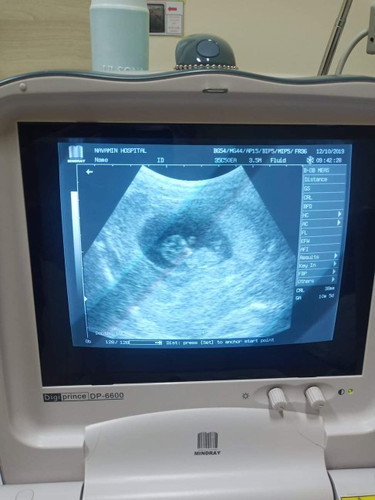

หลังจากที่ซาว3ครั้งไม่เจอตัวเด็กจนมาวันนี้ได้เจอกันแล้วหนูดิ้นดุกดิกๆเก่งมาก